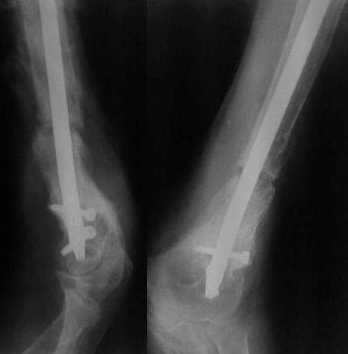

[Ortho] Ложный сустав в/3 плечевой кости!

Более года назад пациент был оперирован в одном из НИИТО. При

контрольном осмотре через год: болевой синдром, контрактура в

локтевом суставе, патологическая подвижность нижней трети плеча